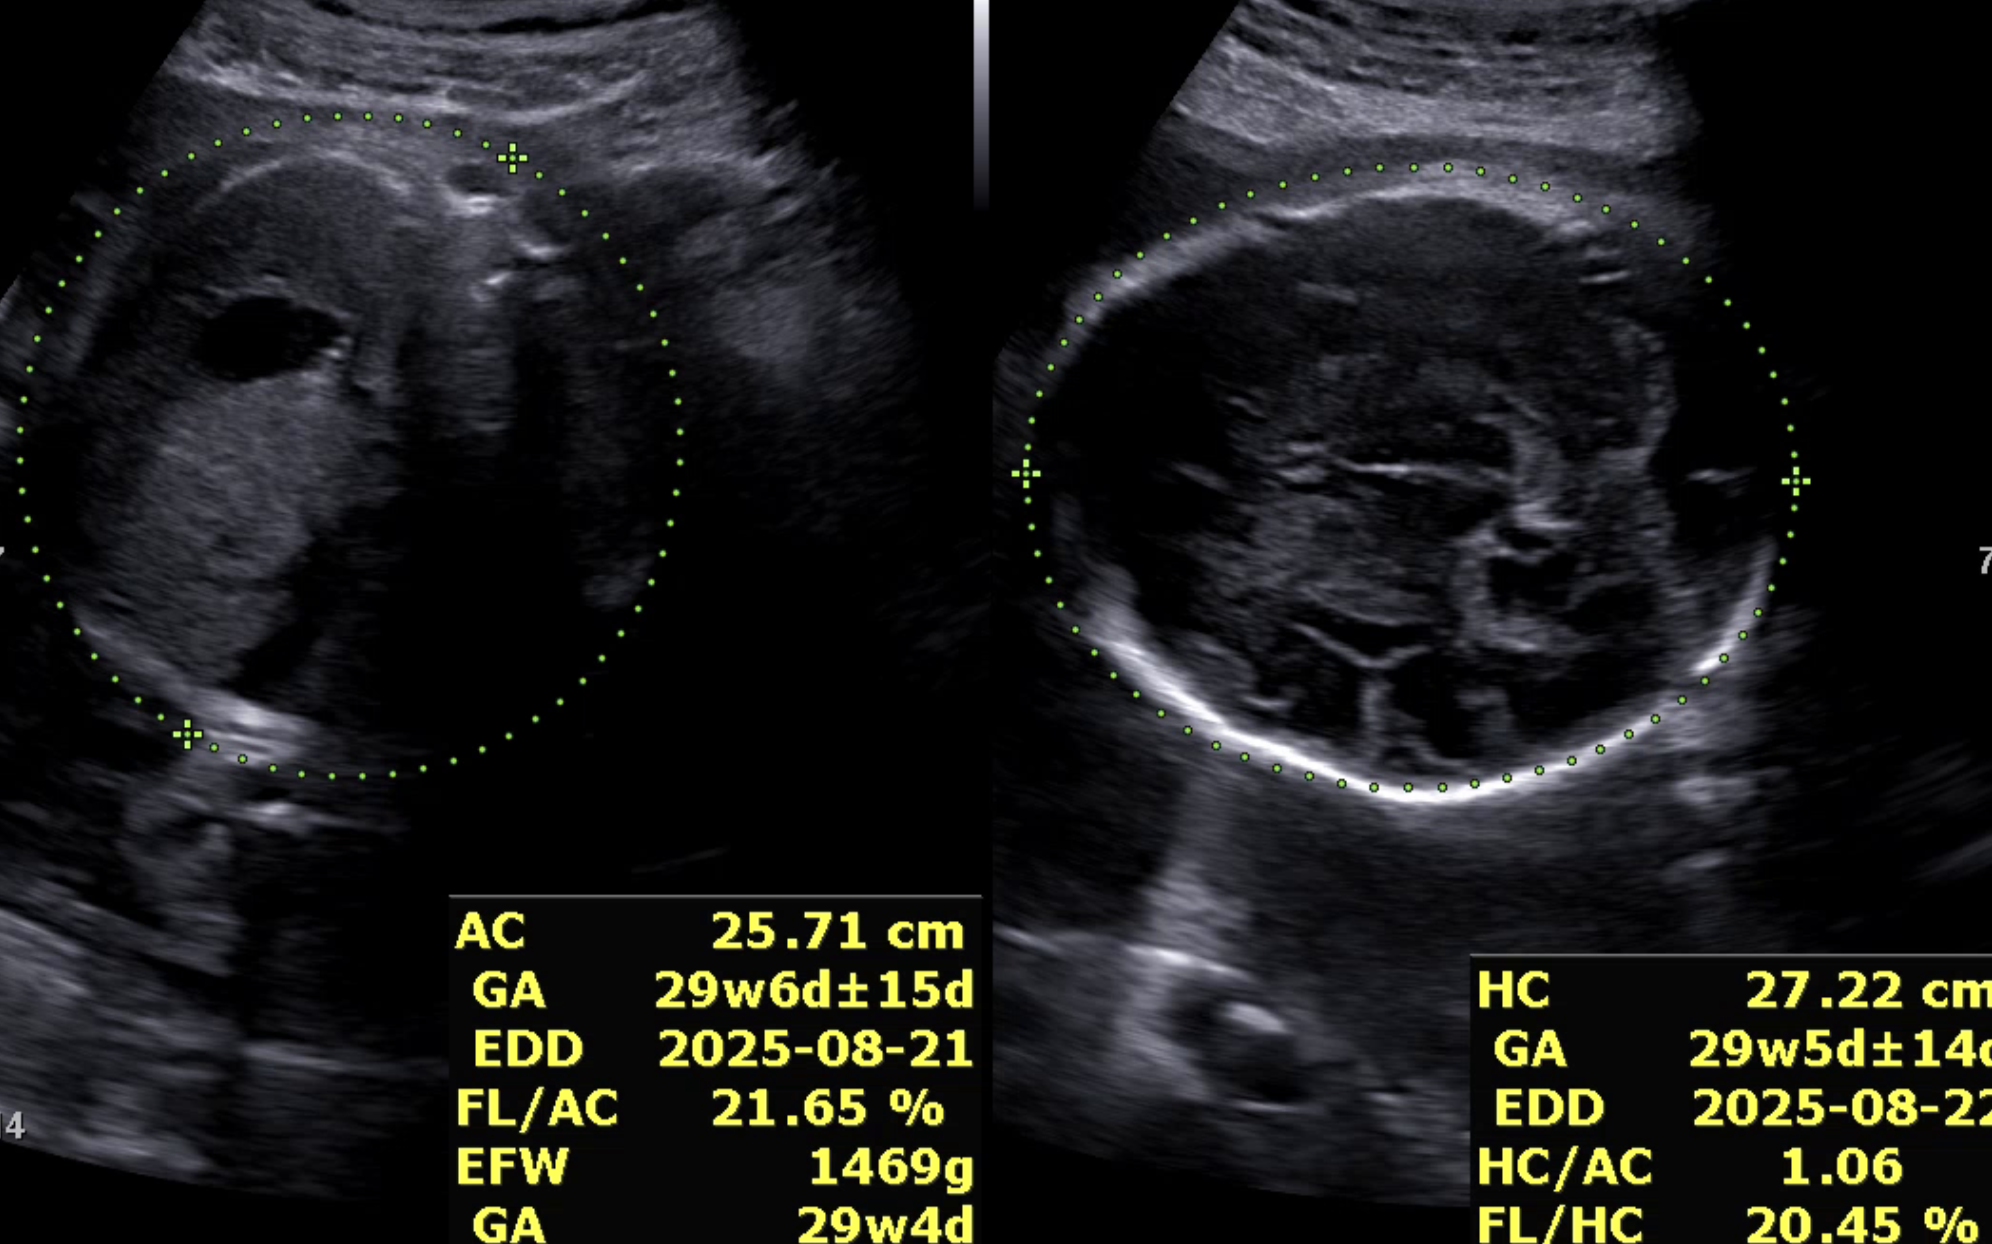

모델이 더 안정적으로 학습하려면 초반부터 모든 데이터를 학습에 사용하고, 확신이 없는 데이터까지 포함하도록 변경했다. 하지만 무엇보다도, 초음파 이미지라는 특성상 한 장의 이미지에 여러 부위가 함께 측정되는 경우도 많다는 사실을 간과하고 있었다. 실제 의료진도 하나의 이미지에서 AC, FL 등 여러 부위를 동시에 측정한다. 하지만 softmax 기반의 멀티 클래스 분류 방식은 무조건 하나의 클래스만 선택해야 하기 때문에, 이런 현실적인 상황을 반영하지 못했다. 결과적으로, 데이터 자체는 멀티 클래스 특성을 가지고 있는데, 모델은 억지로 싱글 클래스로 억지로 해석하고 있었다.

아래는 멀티 클래스 기반으로 변경한 뒤의 실제 예측 결과 예시이다. 단일 클래스 방식에서는 하나의 부위만 예측되던 이미지에서, 이제는 여러 부위가 동시에 높은 확률로 예측되는 모습을 확인할 수 있다.